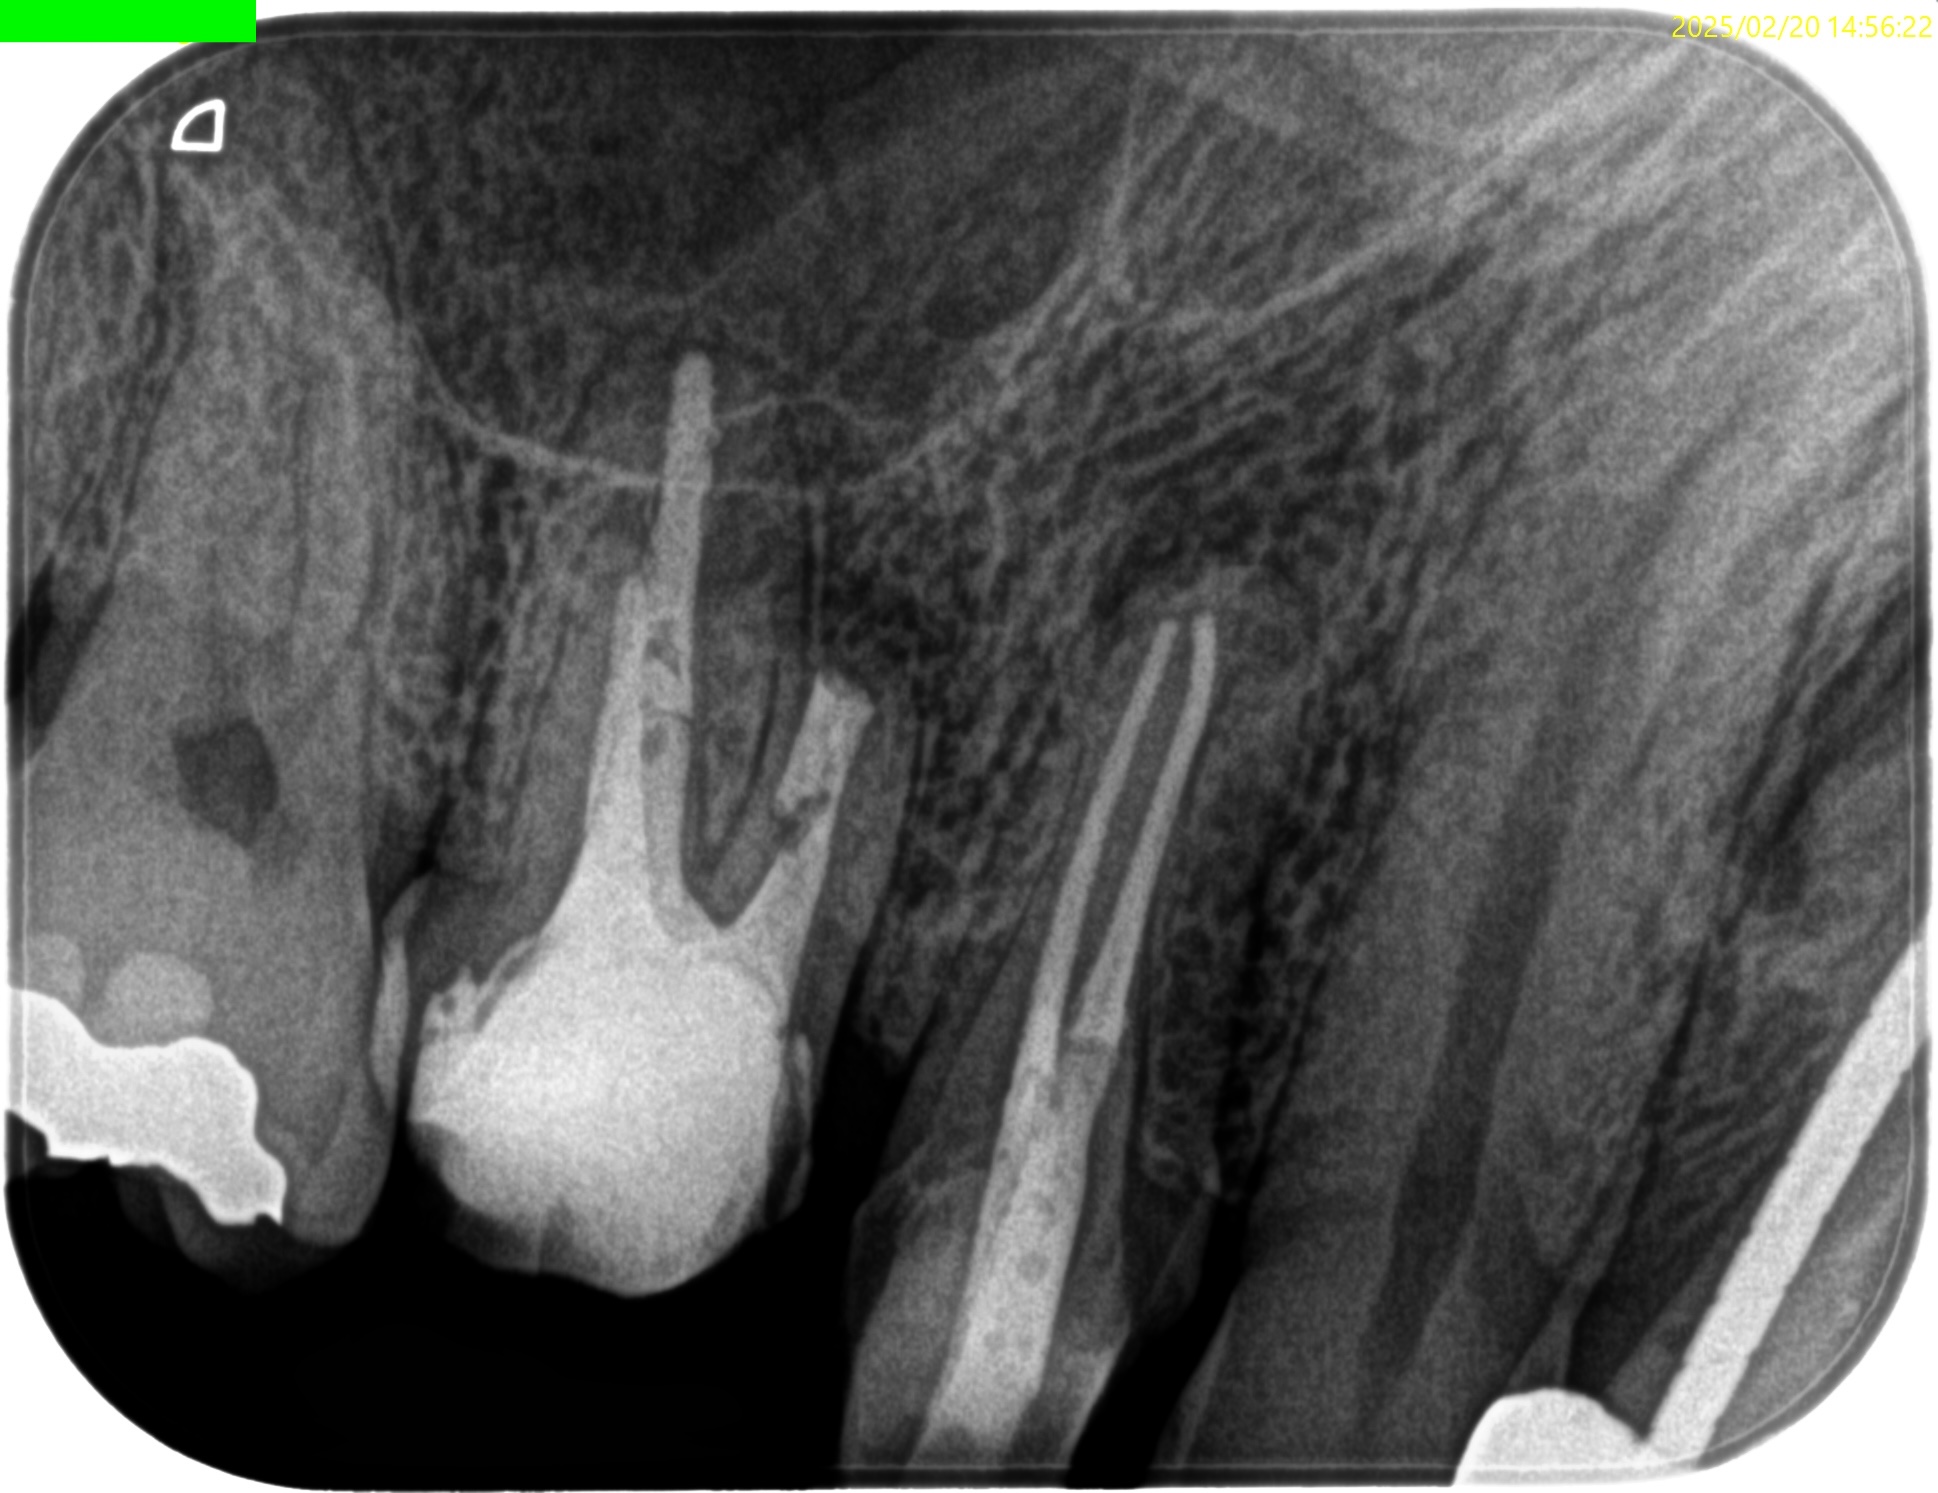

#3 MB Apicoectomy(2025.2.20)

#3 MBのApexは容易に発見できた。

このまま3mmで切断する。

その際は、頬舌的に4.5mm切断しなくてはならない。

大した距離ではないので容易だろう。

切断面は、

この形態と相似形なので問題はないだろう。

そして、この形態の中心にGutta Perchaが存在し、近傍にMB2があることが予想される。

頬舌的に超音波を動かさなくて済むのである。

かなりEasyだ。

ということで、逆根管形成した。

最後に逆根管充填した。

この時、シーラー

エンドセム MTA クイックペースト R

だけで逆根管充填している。

充填後、CBCTとPAを撮影した。

問題はないだろう。